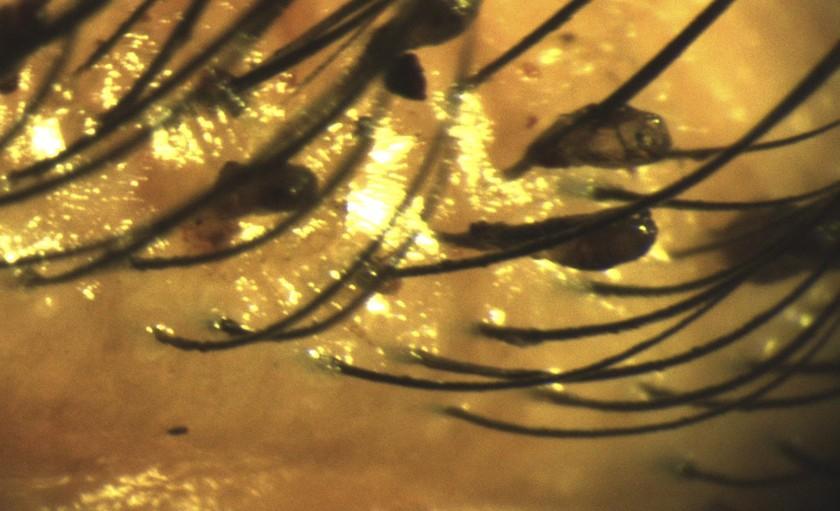

Ổ rận mu làm tổ trên mi mắt người bệnh. Ảnh: BVCC

Tại bệnh viện, bệnh nhân được kiểm tra mắt dưới kính hiển vi và được phát hiện nhiều ký sinh trùng và trứng ký sinh trên mi mắt.

Bác sĩ đã tiến hành gây tê tại chỗ và lấy ra hàng chục kí sinh trùng rận mu và trứng ký sinh, đồng thời vệ sinh khu vực mắt bằng dung dịch chuyên dụng, và kê đơn thuốc chỉ định cho bệnh nhân sử dụng tại nhà.